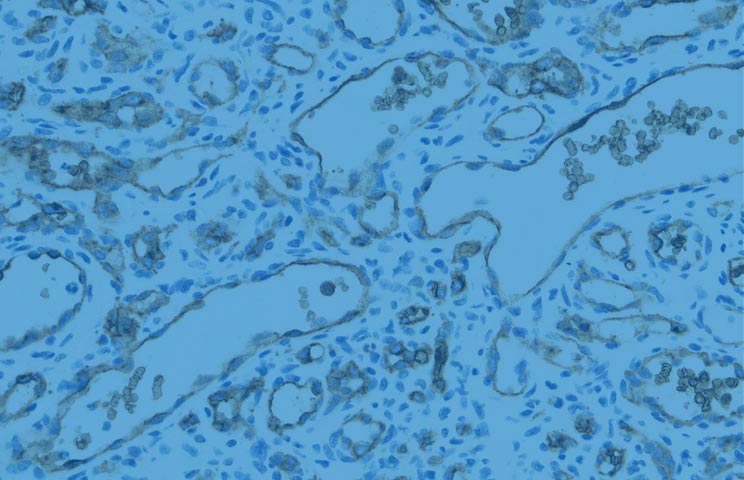

Infections Stomach cancer

Researchers from the International Agency for Research on Cancer (IARC) and the National Cancer Center of the Republic of Korea marked 10 years since initiating the collaborative study on the Effect of Helicobacter pylori Eradication on Gastric Cancer Prevention (HELPER) in the Republic of Korea by holding meetings with research staff and investigators from 12 study centres throughout the country during March 2024.

The HELPER study is a randomized controlled clinical trial to evaluate the effect of H. pylori eradication for gastric cancer prevention among a study population of almost 12 000 participants.